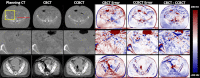

Purpose: The incorporation of cone-beam computed tomography (CBCT) has allowed for enhanced image-guided radiation therapy. While CBCT allows for daily 3D imaging, images suffer from severe artifacts, limiting the clinical potential of CBCT. In this work, a deep learning-based method for generating high quality corrected CBCT (CCBCT) images is proposed.

Methods: The proposed method integrates a residual block concept into a cycle-consistent adversarial network (cycle-GAN) framework, called res-cycle GAN, to learn a mapping between CBCT images and paired planning CT images. Compared with a GAN, a cycle-GAN includes an inverse transformation from CBCT to CT images, which constrains the model by forcing calculation of both a CCBCT and a synthetic CBCT. A fully convolution neural network with residual blocks is used in the generator to enable end-to-end CBCT-to-CT transformations. The proposed algorithm was evaluated using 24 sets of patient data in the brain and 20 sets of patient data in the pelvis. The mean absolute error (MAE), peak signal-to-noise ratio (PSNR), normalized cross-correlation (NCC) indices, and spatial non-uniformity (SNU) were used to quantify the correction accuracy of the proposed algorithm. The proposed method is compared to both a conventional scatter correction and another machine learning-based CBCT correction method.

Results: Overall, the MAE, PSNR, NCC, and SNU were 13.0 HU, 37.5 dB, 0.99, and 0.05 in the brain, 16.1 HU, 30.7 dB, 0.98, and 0.09 in the pelvis for the proposed method, improvements of 45%, 16%, 1%, and 93% in the brain, and 71%, 38%, 2%, and 65% in the pelvis, over the CBCT image. The proposed method showed superior image quality as compared to the scatter correction method, reducing noise and artifact severity. The proposed method produced images with less noise and artifacts than the comparison machine learning-based method.